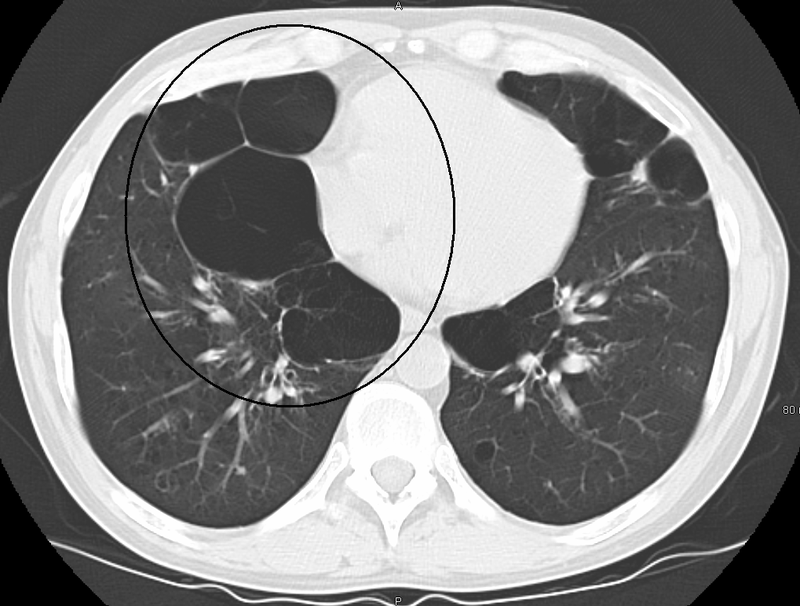

• Bronchiectasis

Bronchiectasis. CT scan of the lungs showing findings diagnostic of bronchiectasis. White and black arrows point to dilated bronchi characteristic of the disease. Mcgfowler. Not altered. CC BY-SA 3.0